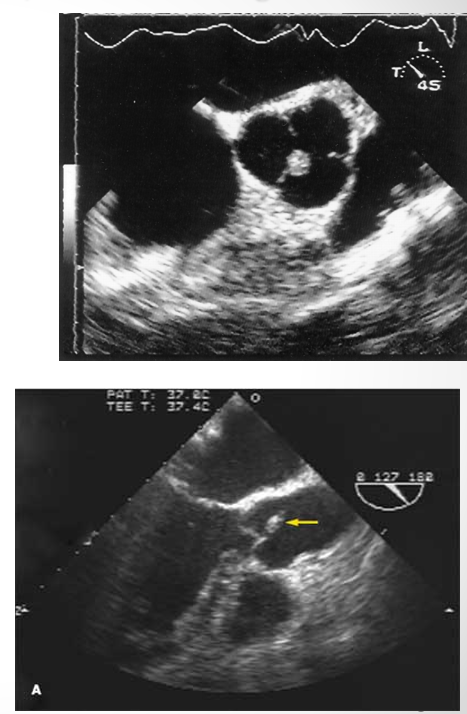

what is seen here?

periannular absces adjacent to sewing ring